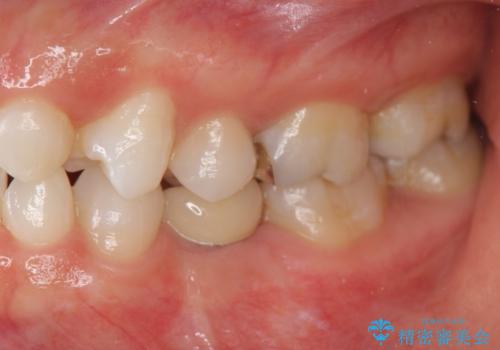

乳歯の残存 インプラントによる置き換え

- 大人になっても残存していた乳歯がグラグラし、痛くて噛めない 抜いて欲しいとの希望で来院されました。

歯根が吸収し残すことのできない乳歯を抜去後、隣の歯を削らずに済むインプラント治療で咬合機能の回復を計画します。

乳歯の抜去後、インプラントを用いてしっかりと咬合機能を回復することができました。